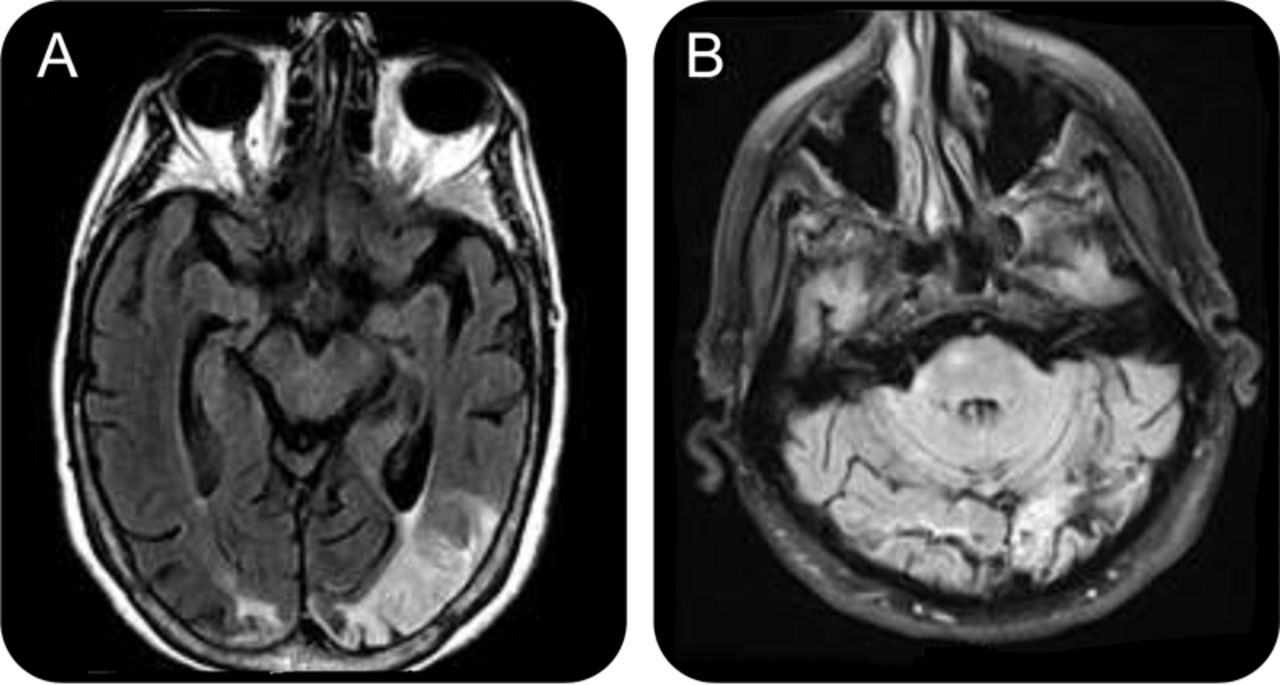

A.S.和J.D.出现不同的故事乍看之下,但他们实际上是两个描述的一种罕见的神经系统疾病的发病Balint综合症。Balint综合症通常是由一个或多个缺血性中风顶叶和枕叶皮层。磁共振(MR)研究显示,一家有一系列cardioembolic梗塞包括顶叶和枕叶皮质,双边(图)。J.D.可能有一系列的缺血性梗塞由于严重的动脉粥样硬化vertebrobasilar疾病(图,B)。

图像从病人(A)和病人J.D. (B)显示双边para-calcarine缺血与二级小出血性改变拉伸壁混杂在一起。